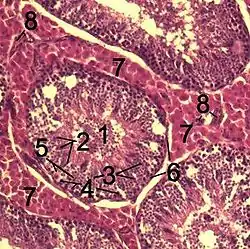

![]() Histological section through testicular parenchyma of a boar. 1 Lumen of convoluted part of the seminiferous tubules, 2 spermatids, 3 spermatocytes, 4 spermatogonia, 5 Sertoli cell, 6 myofibroblasts, 7 Leydig cells, 8 capillaries | |

Leydig cells, also known as interstitial cells of the testes and interstitial cells of Leydig, are found adjacent to the seminiferous tubules in the testicle and produce testosterone in the presence of luteinizing hormone (LH).[1][2] They are polyhedral in shape and have a large, prominent nucleus, an eosinophilic cytoplasm, and numerous lipid-filled vesicles.[3]

The mammalian Leydig cell is a polyhedral epithelioid cell with a single eccentrically located ovoid nucleus. The nucleus contains one to three prominent nucleoli and large amounts of dark-staining peripheral heterochromatin. The acidophilic cytoplasm usually contains numerous membrane-bound lipid droplets and large amounts of smooth endoplasmic reticulum (SER).[4] Besides the abundance of SER with scattered patches of rough endoplasmic reticulum, several mitochondria are also prominent within the cytoplasm. Reinke crystals have lipofuscin pigment and rod-shaped crystal-like structures 3 to 20 micrometres in diameter.[5]